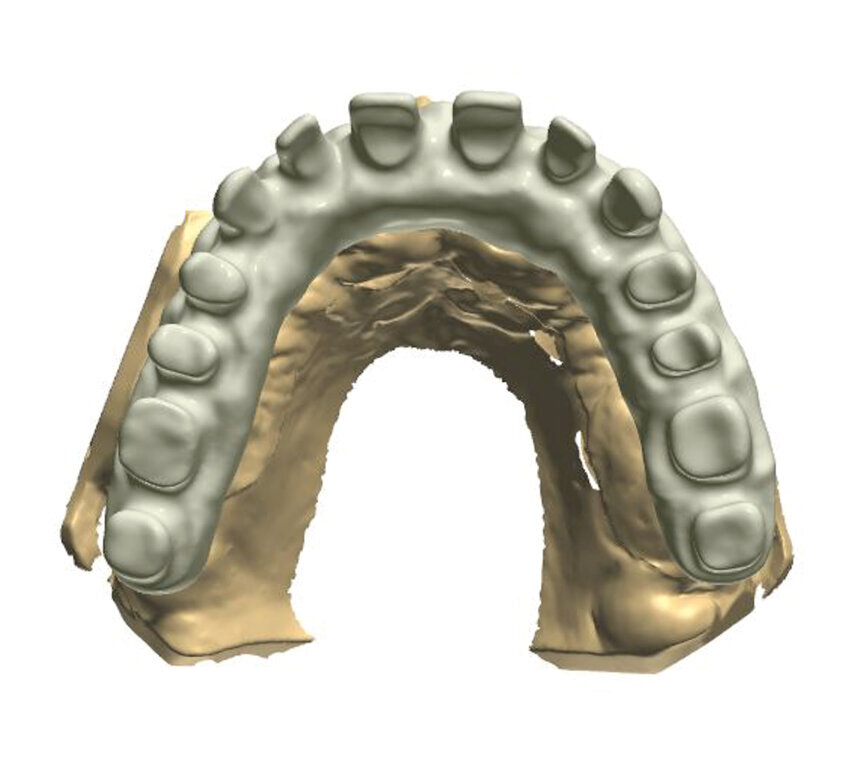

Fig. 1: A virtual image of a scanned model with abutments and telescopic crowns.

In order to prepare the bridge, a model was scanned and transferred onto a computer using software to design the bar (Fig. 1). The bar was designed by using special software in such a way that the whole design was transparent in the first phase so that the location of abutments and the position of the telescopic abutments at the frontal section could be visible (Fig. 2).